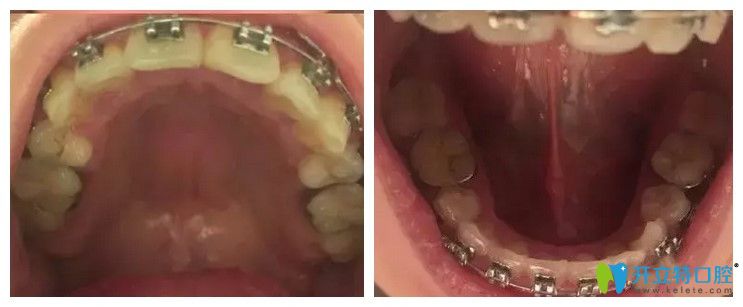

<戴金屬牙套即將畢業(yè)的口內(nèi)照片>:↓↓

戴金屬牙套即將畢業(yè)的口內(nèi)照片